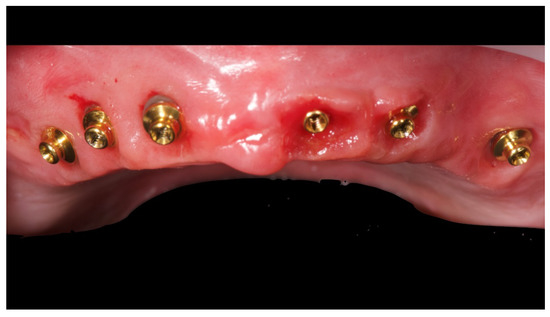

Figure 5.

Intraoral picture of the implant positions and the multi-unit abutment screwed on.